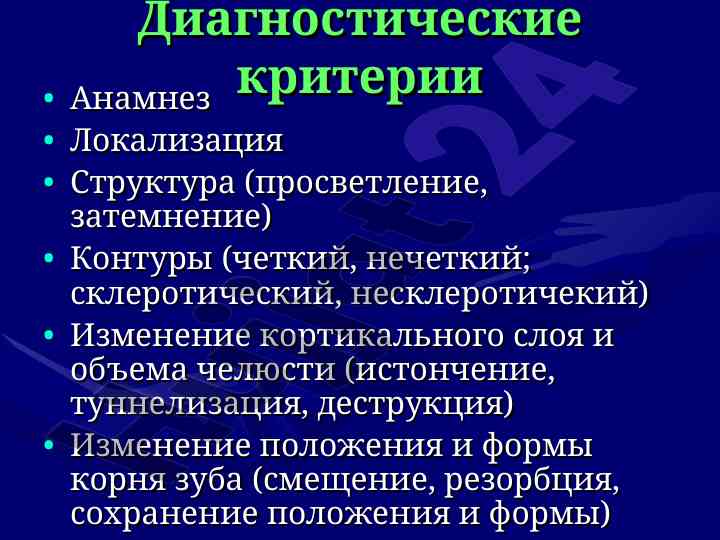

Диагностика и характеристики кист чло

Данная лекция охватывает диагностические критерии, локализацию и структуру кист и опухолей челюстно-лицевой области, включая одонтогенные и неодонтогенные кисты.